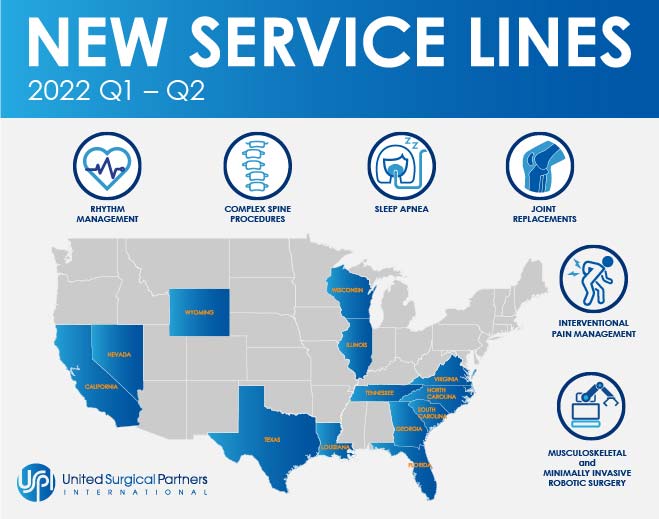

USPI Enhances Capabilities with New Service Lines in 1H'22